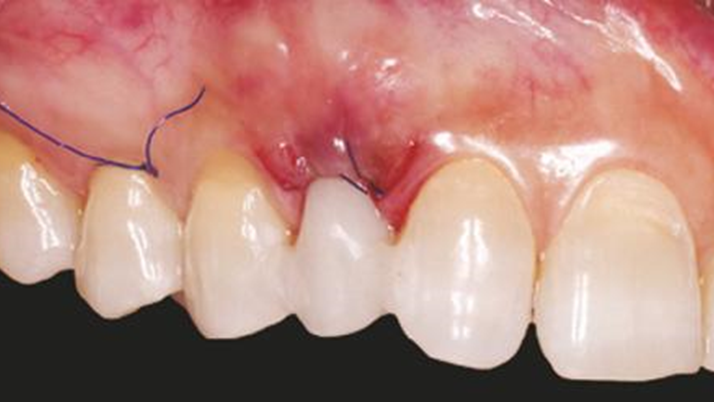

Clinical case: BPET PREDICTABILITY - State-of-the-Art SOCKET SHIELD

- Courtesy of Dr. Howard Gluckman, South Africa -

“AnyRidge is perfect for the anterior esthetic zone due to its strong initial stability & fast osseointegration.

Plus, KnifeThread® ensures space maintenance when using the PET/Socket Shield/Root Membrane Technique, showing excellent bone growth.”